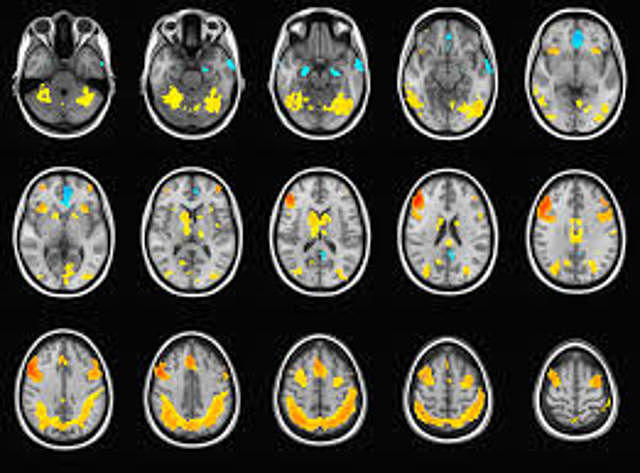

• Se fortalece la investigación con el empleo de imágenes no ya anatómicas sino funcionales, en particular la resonancia magnética y la tomografía han permitido visualizar la actividad cerebral durante la realización de tareas cognoscitivas.

Se fortalece la investigación con el empleo de imágenes no ya anatómicas sino funcionales, en particular la resonancia magnética y la tomografía han permitido visualizar la actividad cerebral durante la realización de tareas cognoscitivas.